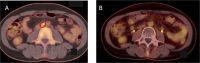

Clear cell adenocarcinoma of the uterine cervix is a rare and aggressive subtype of cervical cancer, typically resistant to conventional radiation therapy and lacking dedicated treatment guidelines. We present the case of a young patient with an ataxia telangiectasia mutation and locally advanced disease, who was unfit for brachytherapy following standard chemoradiotherapy and subsequently received a carbon ion radiation therapy boost. This mixed-beam strategy was well tolerated and led to durable local control along with a nodal response, which is suggestive of a possible abscopal effect. These findings underscore the potential of carbon ion radiation therapy in overcoming radioresistance and suggest a contributory role of genetic background in mediating systemic immune effects.